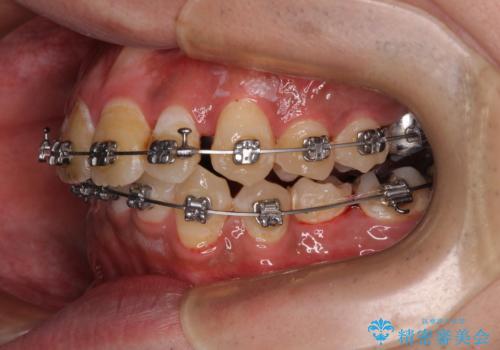

- 矯正装置

- メタルブラケット

- 2年

- 主張してる上の前歯を気にして来院された患者様です。

上の前歯が出ているものの、口元が出っ歯というわけではなかったため、非抜歯矯正にて治療を行うこととしました。

下顎に対して上顎歯列が全体的に前方に位置しており、特に右側の奥歯の咬み合わせの前後のズレが大きいため、補助装置を用いて咬み合わせを改善することとしました。

元々むし歯リスクが高かった上に、矯正治療中も磨き残しが多かったため、今後はむし歯治療を行う必要があります。